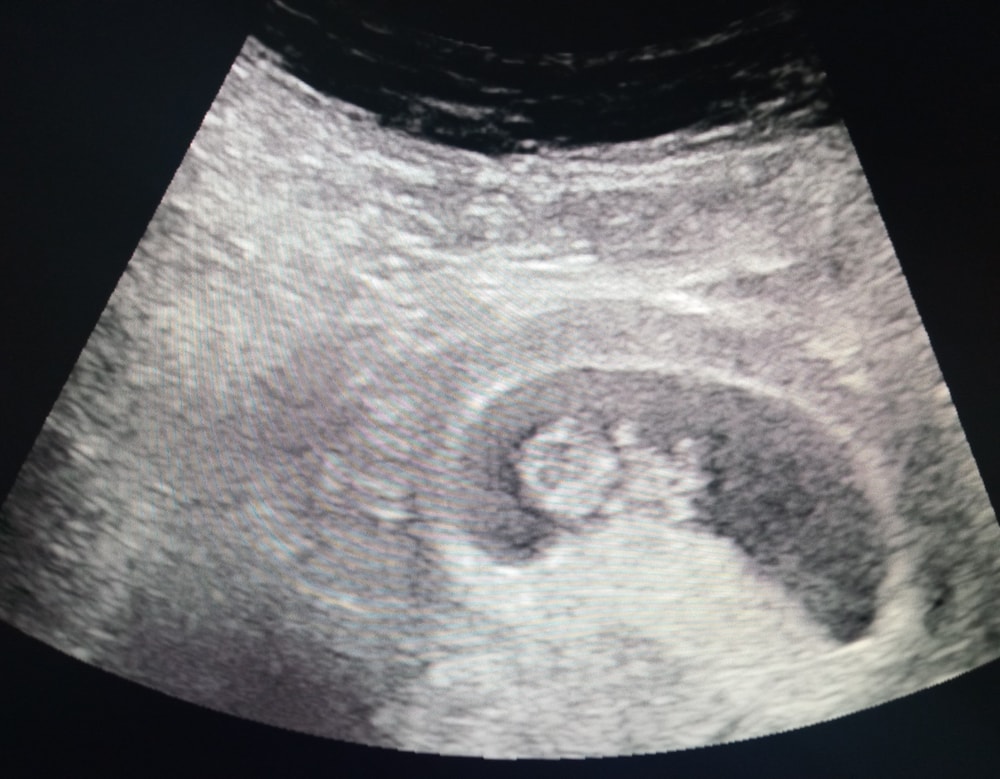

Желточный мешок 5мм в 7-8н

6 недель и 8 недельИзображение Изображение

Mandarin , почему-то уже не мерили, там уже неваляшка была Изображение

Нормальный жм

Нормально. Норма до 6

Тоже волновалась по поводу жм. Перерыла пол интернета. В 7 и 5 он у меня был 5.7!! Но, мне кажется, что замерили неправильно, так как ободок не должен измеряться, а только черное пространство. Поэтому возможный размер 5.4. В итоге, все в порядке на скрининге, скрининг крови тоже хороший, мешочка в 12 недель уже не было. Думаю, что все хорошо у вас!